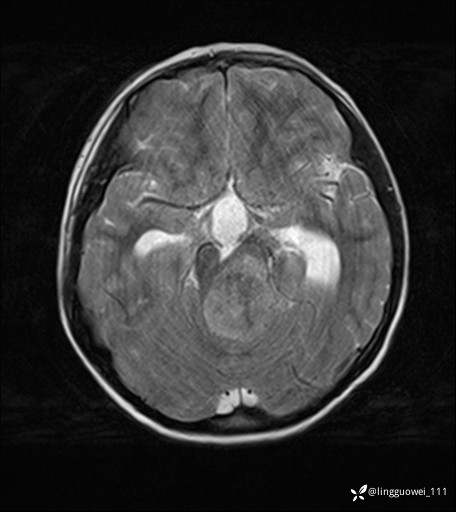

男,8岁,外伤后发现颅内占位,定位定性,4天后公布结果。

患者性别:男

患者年龄:8岁。

主诉:外伤后发现颅内占位。

外院做的手术,术后回本院复查,只有平扫,定位在哪?良性还是恶性?

T2